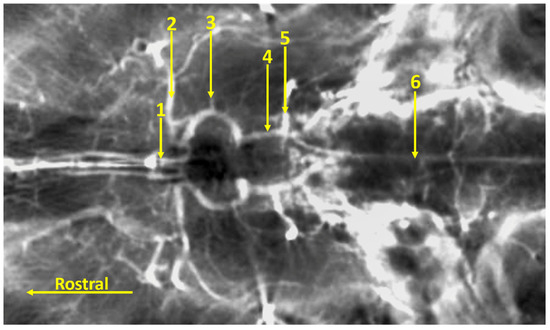

3. Results